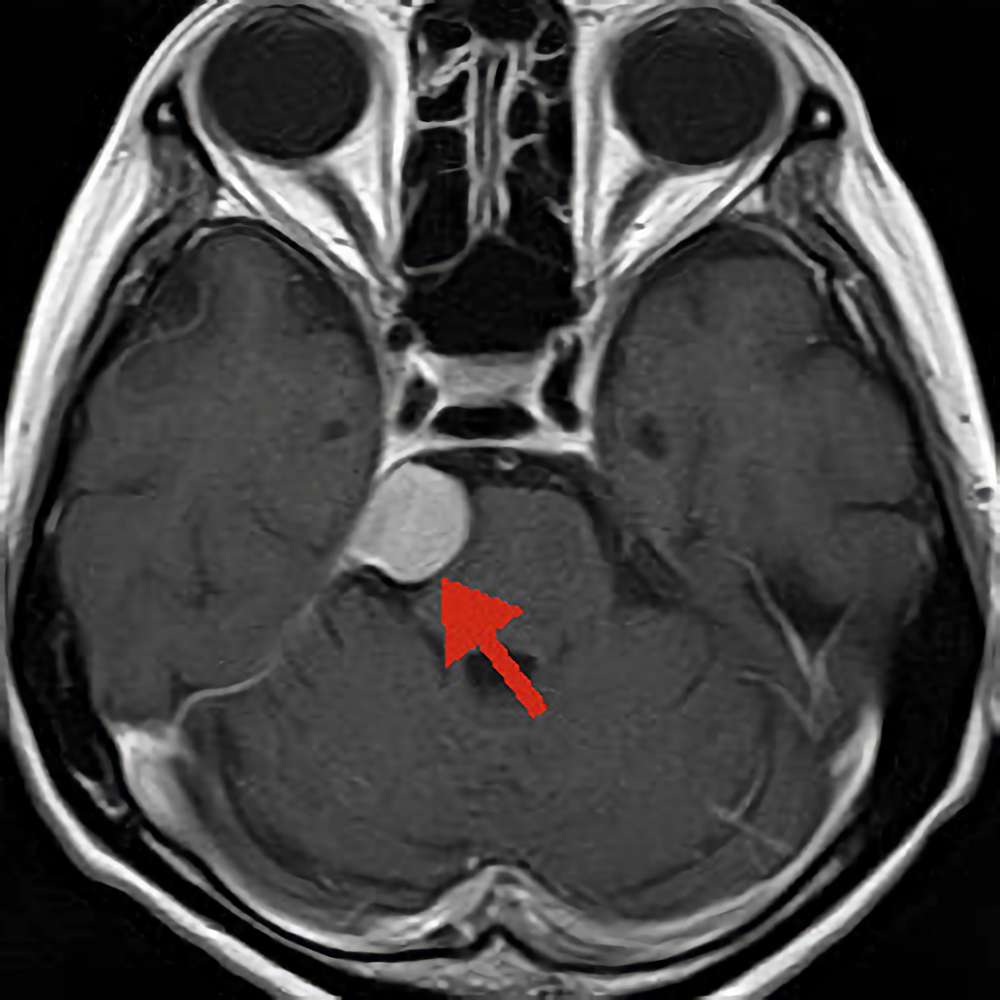

聴神経鞘腫

No.’14_1 手術前1

No.’14_1 摘出 前

No.’14_1 摘出 後